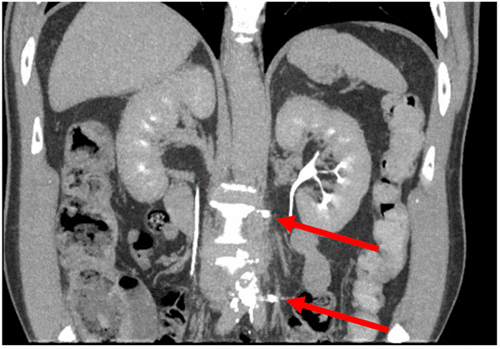

In anticipation of a technically challenging dissection due to prior surgery and radiation, MOLLI Markers® (magnetic seeds) were placed percutaneously by interventional radiology under CT guidance two weeks before the planned operation. These markers were positioned just cephalad and caudal to the recurrent lesion to facilitate intraoperative localization (Figure 2). A left ureteric stent was also placed preoperatively. The abdomen was entered via a lower midline incision, and the aortic bifurcation was exposed. The MOLLI markers were easily identified using a handheld magnetic probe, and superficial marking stitches were placed on the overlying retroperitoneal tissues to visually bracket the target area. Dissection revealed a short IMA remnant coursing leftward over the fibrotic tumor mass. Consistent with the patient's history, all surgical planes were densely fibrotic. The MOLLI markers proved critical in guiding the vertical extent of the dissection. The most demanding portion of the procedure involved sharp dissection to develop a plane between the adventitia of the aorta and the recurrent tumor mass.

Figure 2. CT Confirmation of Magnetic Seed (MOLLI Marker®) Placement. Published with Permission

Coronal reformatted CT scan obtained after percutaneous, image-guided placement of MOLLI Markers®. The image demonstrates the precise positioning of the magnetic seeds (arrows) bracketing the recurrent para-aortic lesion, confirming their suitability for intraoperative localization